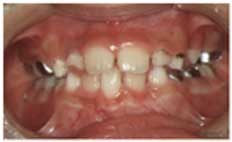

27. 交叉咬合の治療例

子供の時の交叉咬合は、比較的短期間で治療が可能です。どの歯をどの方向に動かすかを決定し、その動きにあった、一番望ましい装置で治療します。